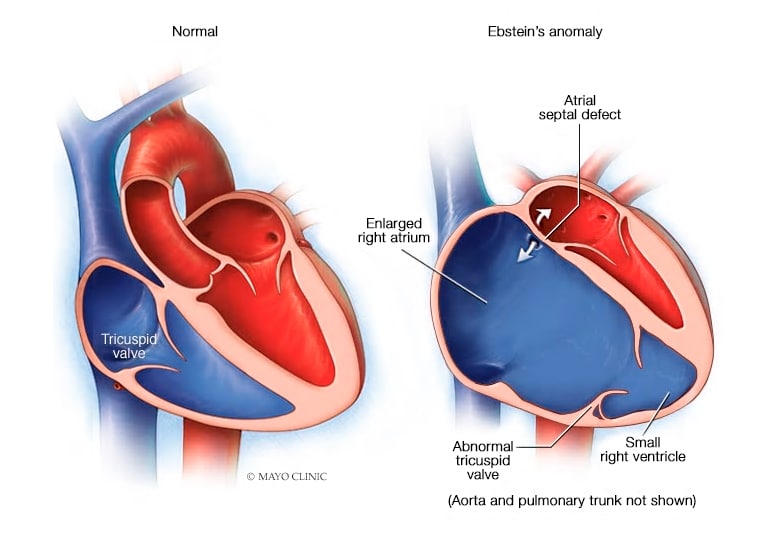

A greater appreciation of normal and abnormal anatomy is important as new methods of treating the tricuspid regurgitation are developed. It opens during diastole and closes during systole. The tricuspid valve tv is a complex structure.

A the anatomy of the tricuspid valve and adjacent structures from a surgical view. Anatomy of the tricuspid valve. The tricuspid valve anatomy shows greater variability than the anatomy of the mitral valve.

In normal heart the tricuspid valve is located slightly closer to the apex than the mitral valve. The red dotted lines show the direction of dilation of various structures in the setting of secondary tricuspid regurgitation. Unlike the aortic and mitral valve it is not possible to visualize all tv leaflets simultaneously in one cross sectional view by standard two dimensional echocardiography 2de either transthoracic or transesophageal due to the position of tv in the far field.